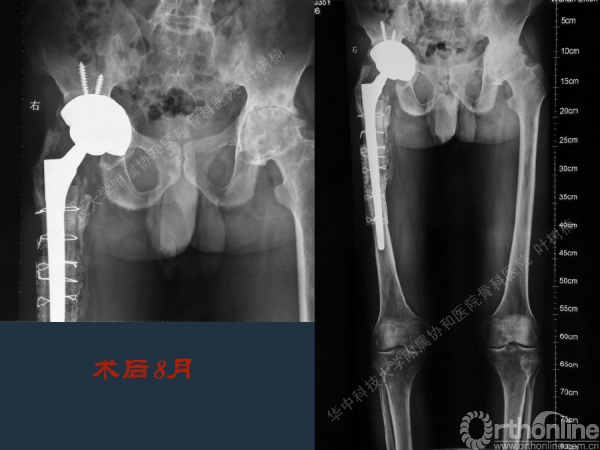

股骨侧翻修

髋臼缺损的处理